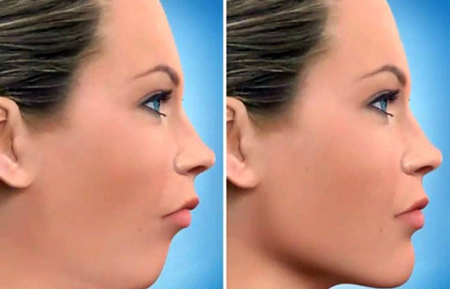

نتیجه جراحی فک

اصلاح بینظمی های فکین و دندان ها در جراحی فک میتواند منجر به:

– تعادل و تقارن نیمه پایینی صورت

باعث بهبود ظاهری و افزایش اعتماد به نفس شود.

اصلاح طرح لبخند